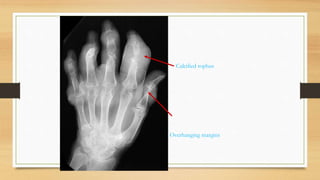

Radiology

• Soft tissue swelling

• Joint space narrowing

• Tophi appear as characteristic punched out “cysts”

• Deep erosion in para-articular bone ends

Calcified tophus

Overhanging margins